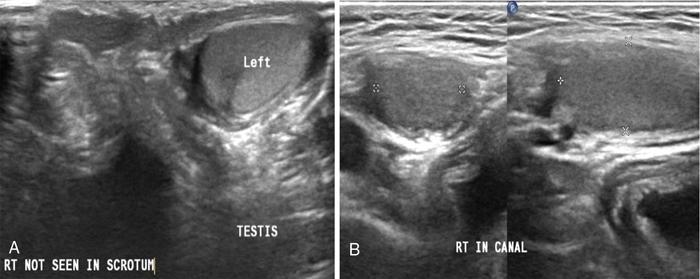

USG findings include empty scrotal sac with UDT usually small, iso- or hypoechoic relative to normal testis. Palpable UDT is most frequently seen in inguinal canal or suprascrotal region just caudal to external inguinal ring (Figs. 11.8.4–11.8.6). Retractile testis at suprascrotal location can be brought down by probe manoeuvre.

Fig. 11.8.3Inguinal US scan of a 2-month-old male child shows undescended right testis (UDT in cursors) at superficial inguinal ring with associated inguinal hernia (RIH). Clinically the child presented with empty right hemiscrotum since birth.

Fig. 11.8.4(A) Scrotal US scan of a 7-year-old male child shows absent right testicle in ipsilateral hemiscrotum, and (B) US scan of right inguinal region shows presence of testicle in inguinal canal (canalicular UDT).

Visibility of nonpalpable intraabdominally located testis is impaired by bowel gases at US, however, with experienced hands the same can be depicted on ultrasound deep to internal inguinal ring, adjacent to iliac vessels and lateral bladder wall. Tracking the cord technique is also a valuable sign in localizing nonpalpable testis (also ectopic testis) (Fig. 11.8.3).